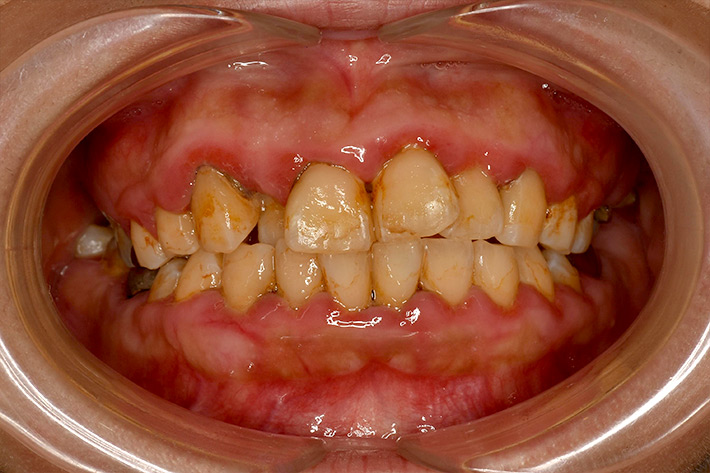

• 国分寺で唯一の「歯周病専門医」

• Periodontal Disease専門医による 重度歯周病治療、 歯周組織再生療法で 歯を残します